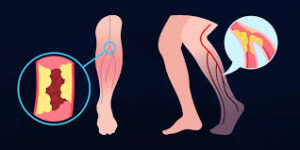

A DAOP consiste no estreitamento ou bloqueio das artérias, principalmente nas pernas, causado pela aterosclerose (acúmulo de...